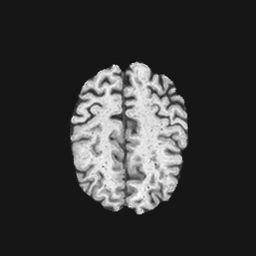

Exp. 1: Segmented adult brain data is used to evaluate our network’s regression performance with known ground truth Tisubscript𝑇𝑖T_{i}. 85 brains from the ADNI data set[1] were randomly selected; 70 brains for ΩtrainsubscriptΩ𝑡𝑟𝑎𝑖𝑛\Omega_{train} and 15 brains for ΩvalidationsubscriptΩ𝑣𝑎𝑙𝑖𝑑𝑎𝑡𝑖𝑜𝑛\Omega_{validation}. Fig. 2 shows an example slice of the ground truth and the reconstructed ΩΩ\Omega.

Figure 2: Example slice from the segmented adult brain MRI data set (a); reconstruction from 300 ωisubscript𝜔𝑖\omega_{i} based on SVRNet regression without SVR (b); SVR initialised with SVRNet predictions after eight iterations of SVR (c). Note that SVRNet (b) predicts individual slice transformations only from image intensities without any initial world co-ordinates of the sampled slice. (d) shows the achieved PSNR in dB when comparing the volumes of (b) and (c) to (a).

Reconstructing from Ti^^subscript𝑇𝑖\hat{T_{i}} initialisation without SVR yields a PSNR of 23.7 ±plus-or-minus\pm 1.09; with subsequent SVR the PSNR increases to 29.5±plus-or-minus\pm2.43 when tested on 15 randomly selected test volumes after four iterations of SVR.